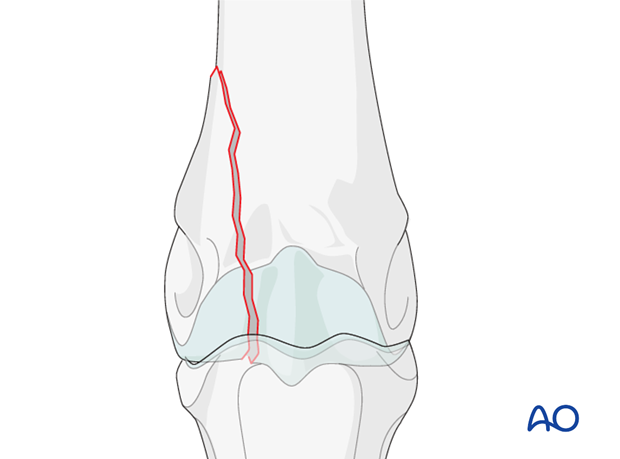

Generally, the fractures tend to develop in the same location of the lateral condyle, several mm lateral to the sagittal ridge, but the height of the fracture can be quite variable.